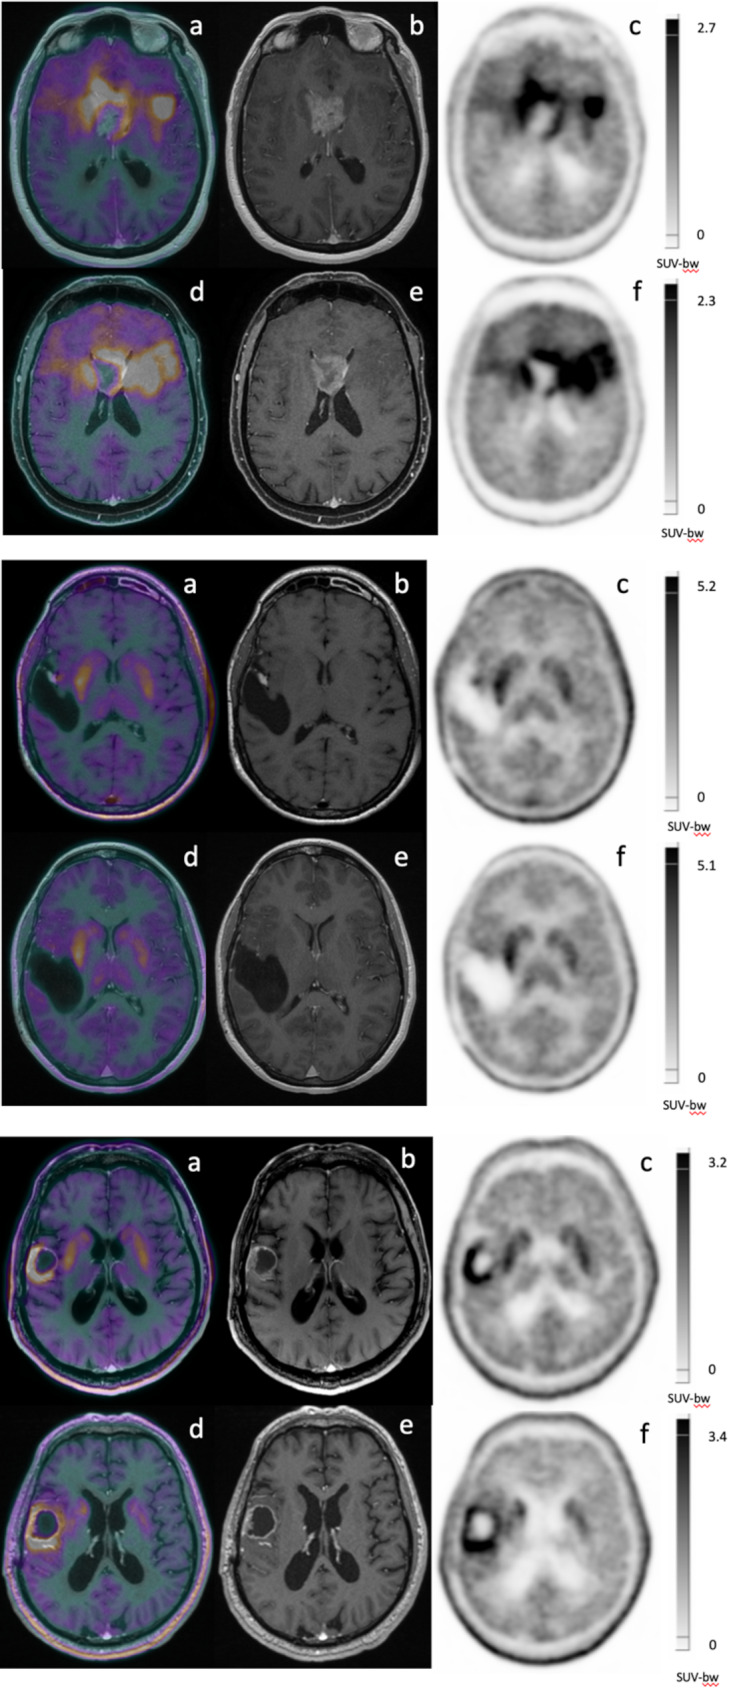

Background: The Response Assessment in Neuro-Oncology (RANO) group recently reported PET-based response assessment criteria for diffuse gliomas (PET RANO 1.0). The objective of this study was to evaluate the methodological application of these criteria for the amino acid [18F]-FDOPA radiotracer. Patients with confirmed glioma who underwent at least one baseline [18F]-FDOPA PET scan were retrospectively included. The PET RANO 1.0 criteria were evaluated regarding their methodological application. Patients with at least one follow-up PET scan were evaluated with the PET RANO 1.0 criteria as compared to the routine interpretation of two experts not using the PET RANO 1.0 criteria, defined as the reference. The different PET parameters included in the PET RANO 1.0 criteria were evaluated separately regarding their contribution.

Results: Ninety patients (52.0 ± 15.3 years old, 56% women) were included in this study regards to the methodology of application of the PET RANO 1.0 criteria, with 86% of patients presenting measurable diseases. Among these patients, 65 patients were evaluated for the comparison between the PET RANO 1.0 criteria and the expert interpretation: a concordance of 80%, equivalent for newly diagnosed and recurrent gliomas, as well as IDH-mutant vs. IDH-wildtype gliomas was found. The metabolic tumor volume represented the most contributive parameter (71% of cases) to the definition of response according to the PET RANO 1.0 criteria. Striatum infiltration, post-treatment related effects, measurable diseases criteria and thresholds for PET RANO 1.0 criteria were related to the cases discordances.

Conclusion: The PET RANO 1.0 criteria can be applied with [18F]-FDOPA imaging, with a reasonable concordance with results of an expert interpretation. Description of discordant cases should help to improve future PET RANO 1.0 criteria updating.